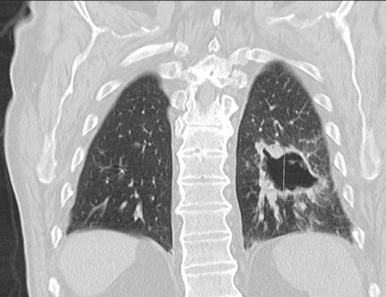

■ Cavitary lesion / nodule (공동성 병변)

§ Solitary cavitary nodules (단일 공동성 결절)

- 공동성 병변은 thick, irregular 한 wall

- 내부에 solid mural component가 존재할 수도 있음.

- 벽의 두께에 따라 4mm 이하 = benign, 15mm 이상일 경우 malignant의 가능성이 높음

- Spiculated(침상형)의 경계를 가질경우 malignant의 가능성 높음

→ ADC와 SCC 모두 공동을 형성 할수 있으나, SCC에서 더 흔함. SCLC는 공동 형성 X

§ Multiple cavitary lesions / nodules (다발 공동성 결절)

- 다발 공동성 병변은 주로 혈관계 전파로 인해 발생한다

- Septic emboli

- Vasculitis : ex) Wegener granulomatosis

- Metastasis :ex) SCC, uterine carcionsarcoma